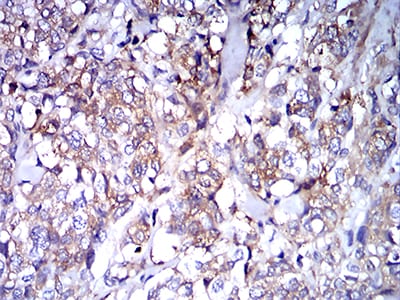

Immunohistochemical analysis of paraffin-embedded human breast cancer tissues using IghA1 mouse mAb with DAB staining.